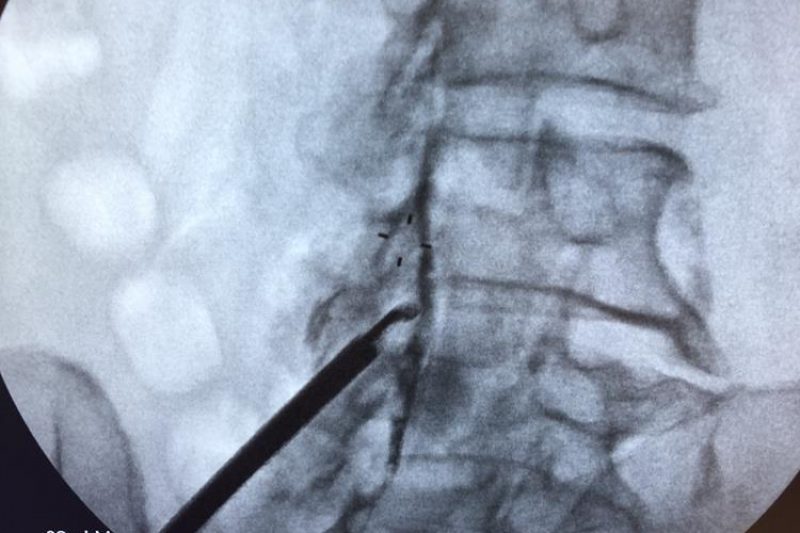

When the protective, cushioning discs between your spinal vertebrae wear down, the soft center can push through and compress the nerves in your spinal canal. This condition, known as …

Herniated discs are one of the most common causes of back and neck pain, creating symptoms that can extend all the way into your arms and legs. When you have …